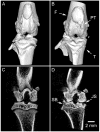

Small-animal imaging has a critical role in phenotyping, drug discovery and in providing a basic understanding of mechanisms of disease. Translating imaging methods from humans to small animals is not an easy task. The purpose of this work is to review in vivo x-ray based small-animal imaging, with a focus on in vivo micro-computed tomography (micro-CT) and digital subtraction angiography (DSA). We present the principles, technologies, image quality parameters and types of applications. We show that both methods can be used not only to provide morphological, but also functional information, such as cardiac function estimation or perfusion. Compared to other modalities, x-ray based imaging is usually regarded as being able to provide higher throughput at lower cost and adequate resolution. The limitations are usually associated with the relatively poor contrast mechanisms and potential radiation damage due to ionizing radiation, although the use of contrast agents and careful design of studies can address these limitations. We hope that the information will effectively address how x-ray based imaging can be exploited for successful in vivo preclinical imaging.